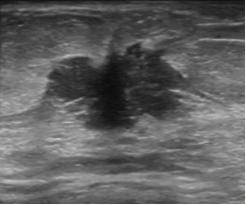

结节内的钙化